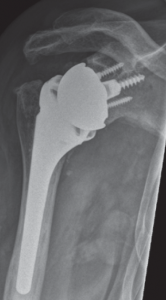

In diesem Fall kann das Gelenk durch ein sog. inverses Prothesen-System nach Prof. Paul Grammont ersetzt werden. Hierbei wird eine „Halbkugel“ (Glenosphäre) auf die ursprüngliche Pfanne aufgeschraubt und eine konvex geformte „Humeruspfanne“ im Oberarmknochen fixiert (Abb. 48). Der Oberarm wird dadurch wieder nach „unten“ verlagert und die Funktion des M. deltoideus wird verbessert (Abb. 49).